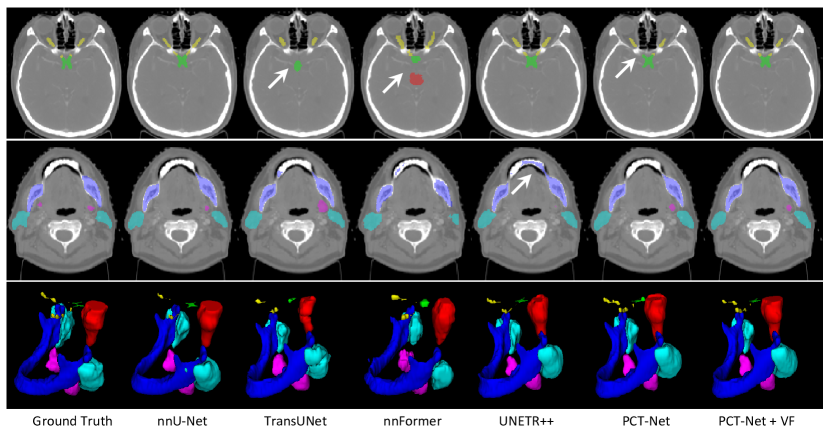

Table 3 shows quantitative evaluation results on the MICCAI 2015 Head-Neck dataset. The nnU-Net [21] achieved an average Dice of 78.66%, with the mandible and optic chiasm being the easiest and hardest OARs to segment, respectively. TransUNet and nnFormer failed to beat nnU-Net, with average Dice of 69.10% and 70.27%, respectively. UNETR++ outperformed nnU-Net with average Dice of 80.37%. Our PCT-Net achieved an average Dice of 81.41%, and performed better than the existing networks. When PCT-Net was pretrained with Volume Fusion, the average Dice was further improved to 82.74%. The average ASSD obtained by PCT-Net + VF was 0.77 mm, which was better than those of the other methods. Fig. 7 shows a visual comparison between the segmentation results obtained by different methods. It can be observed that TransUNet and nnFormer have a poor performance on tiny structures such as optic chiasm and optic nerves. The nnFormer also has an over-segmentation of the brain stem in the first row. UNETR++ has an over-segmentation in the mandible, as shown in the second row. PCT-Net has an overall better performance than these methods, and when pretrained with VF, its performance is further improved, especially for optic nerves as shown in the first row.